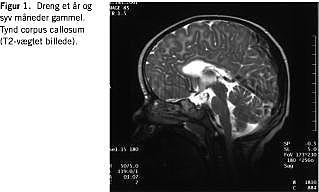

MR-skanningsfund

MR-skanning af cerebrum ved SS viser hypoplasi af corpus callosum og hyperintensitet af den subkorticale hvide substans (indikerer defekt myelinisering) (Figur 1 og Figur 2 ). Svært afficerede patienter har atrofi af cortex, hjernestamme og cerebellum samt cerebellar hypomyelinisering og periventrikulær hyperintensitet [8, 9].